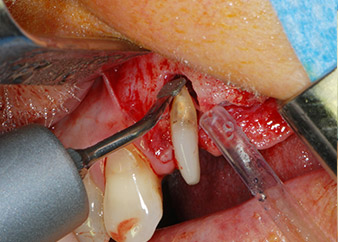

Un mes después, en el día de la intervención, el dolor y la inflamación se habían reducido al mínimo en la pieza 24, pero seguía habiendo una movilidad de clase II de Miller. Después de la apertura de los colgajos y de la limpieza del tejido infectado periapical y perirradicular, la extensión del defecto óseo quedó evidente (figuras 2 y 3).

En primer lugar, en un intento por gestionar el problema endo-periodontal, el resto de la superficie radicular se desbridó con cuidado con un equipo piezoeléctrico (Piezomed de W&H, utilizado con el inserto S1 con forma de espátula, concebido en un principio para la erosión de la pared lateral del seno) (figura 4). A continuación, el ápice se erosionó con el mismo instrumento para eliminar el tejido apical infectado residual y reducir las posibles ramificaciones accesorias del canal radicular (apicectomía) (figura 5). No fue necesario realizar un retrorellleno, puesto que la obturación ortógrada se acababa de revisar.

Fig. 4: Para conservar el diente como un pilar provisional, el periodontio se desbridó utilizando un equipo piezoeléctrico...

ápice bucal

Fig. 5: ... y el ápice bucal de la pieza 24 se erosionó con el mismo inserto (apicectomía).